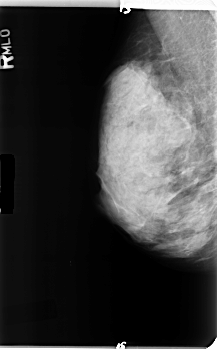

B_3358_1.RIGHT_MLO

RIGHT_MLO LINES 4896 PIXELS_PER_LINE 3032 BITS_PER_PIXEL 12 RESOLUTION 50 NON_OVERLAY